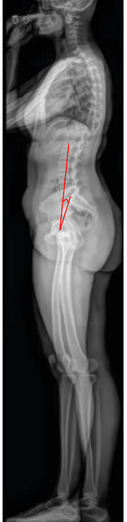

L1 Pelvic Angle (L1PA)

The L1 Pelvic Angle (L1PA) is a radiographic parameter used to evaluate global sagittal alignment by incorporating both spinal inclination and pelvic retroversion.

It is defined as the angle formed between two lines: one connecting the center of the L1 vertebral body to the center of the femoral heads, and the other connecting the center of the S1 endplate to the center of the femoral heads.

The L1PA is a modification of the T1 Pelvic Angle (T1PA) and provides a more lumbar-focused representation of sagittal deformity, particularly useful when upper thoracic landmarks (like T1) are obscured or when analyzing lumbar-pelvic compensation.

It correlates strongly with global sagittal imbalance, lumbar lordosis deficiency, and pelvic tilt, serving as a posture-independent measure of sagittal deformity severity.

• Line 1: from the center of L1 to the center of the femoral heads.

• Line 2: from the center of S1 endplate to the center of the femoral heads.

• Measure the angle formed between Line 1 and Line 2 — this is the L1 Pelvic Angle (L1PA).